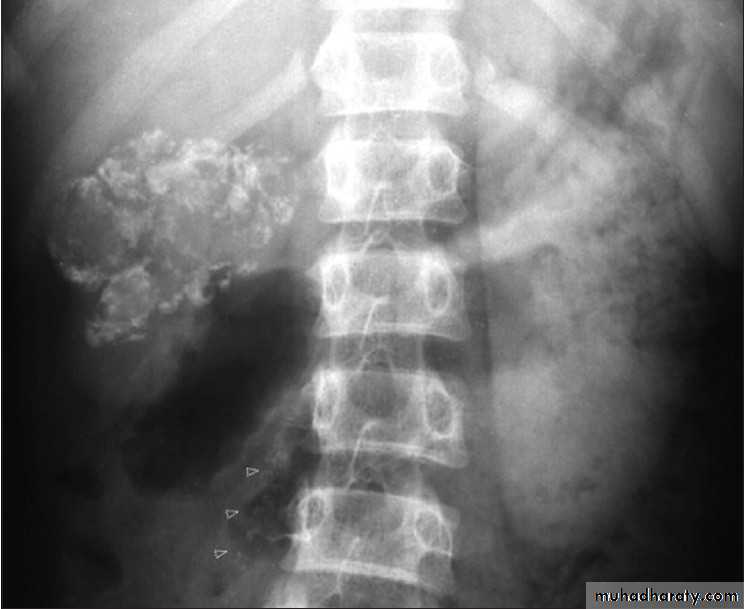

SerologyPlain X-ray

U/S

CT